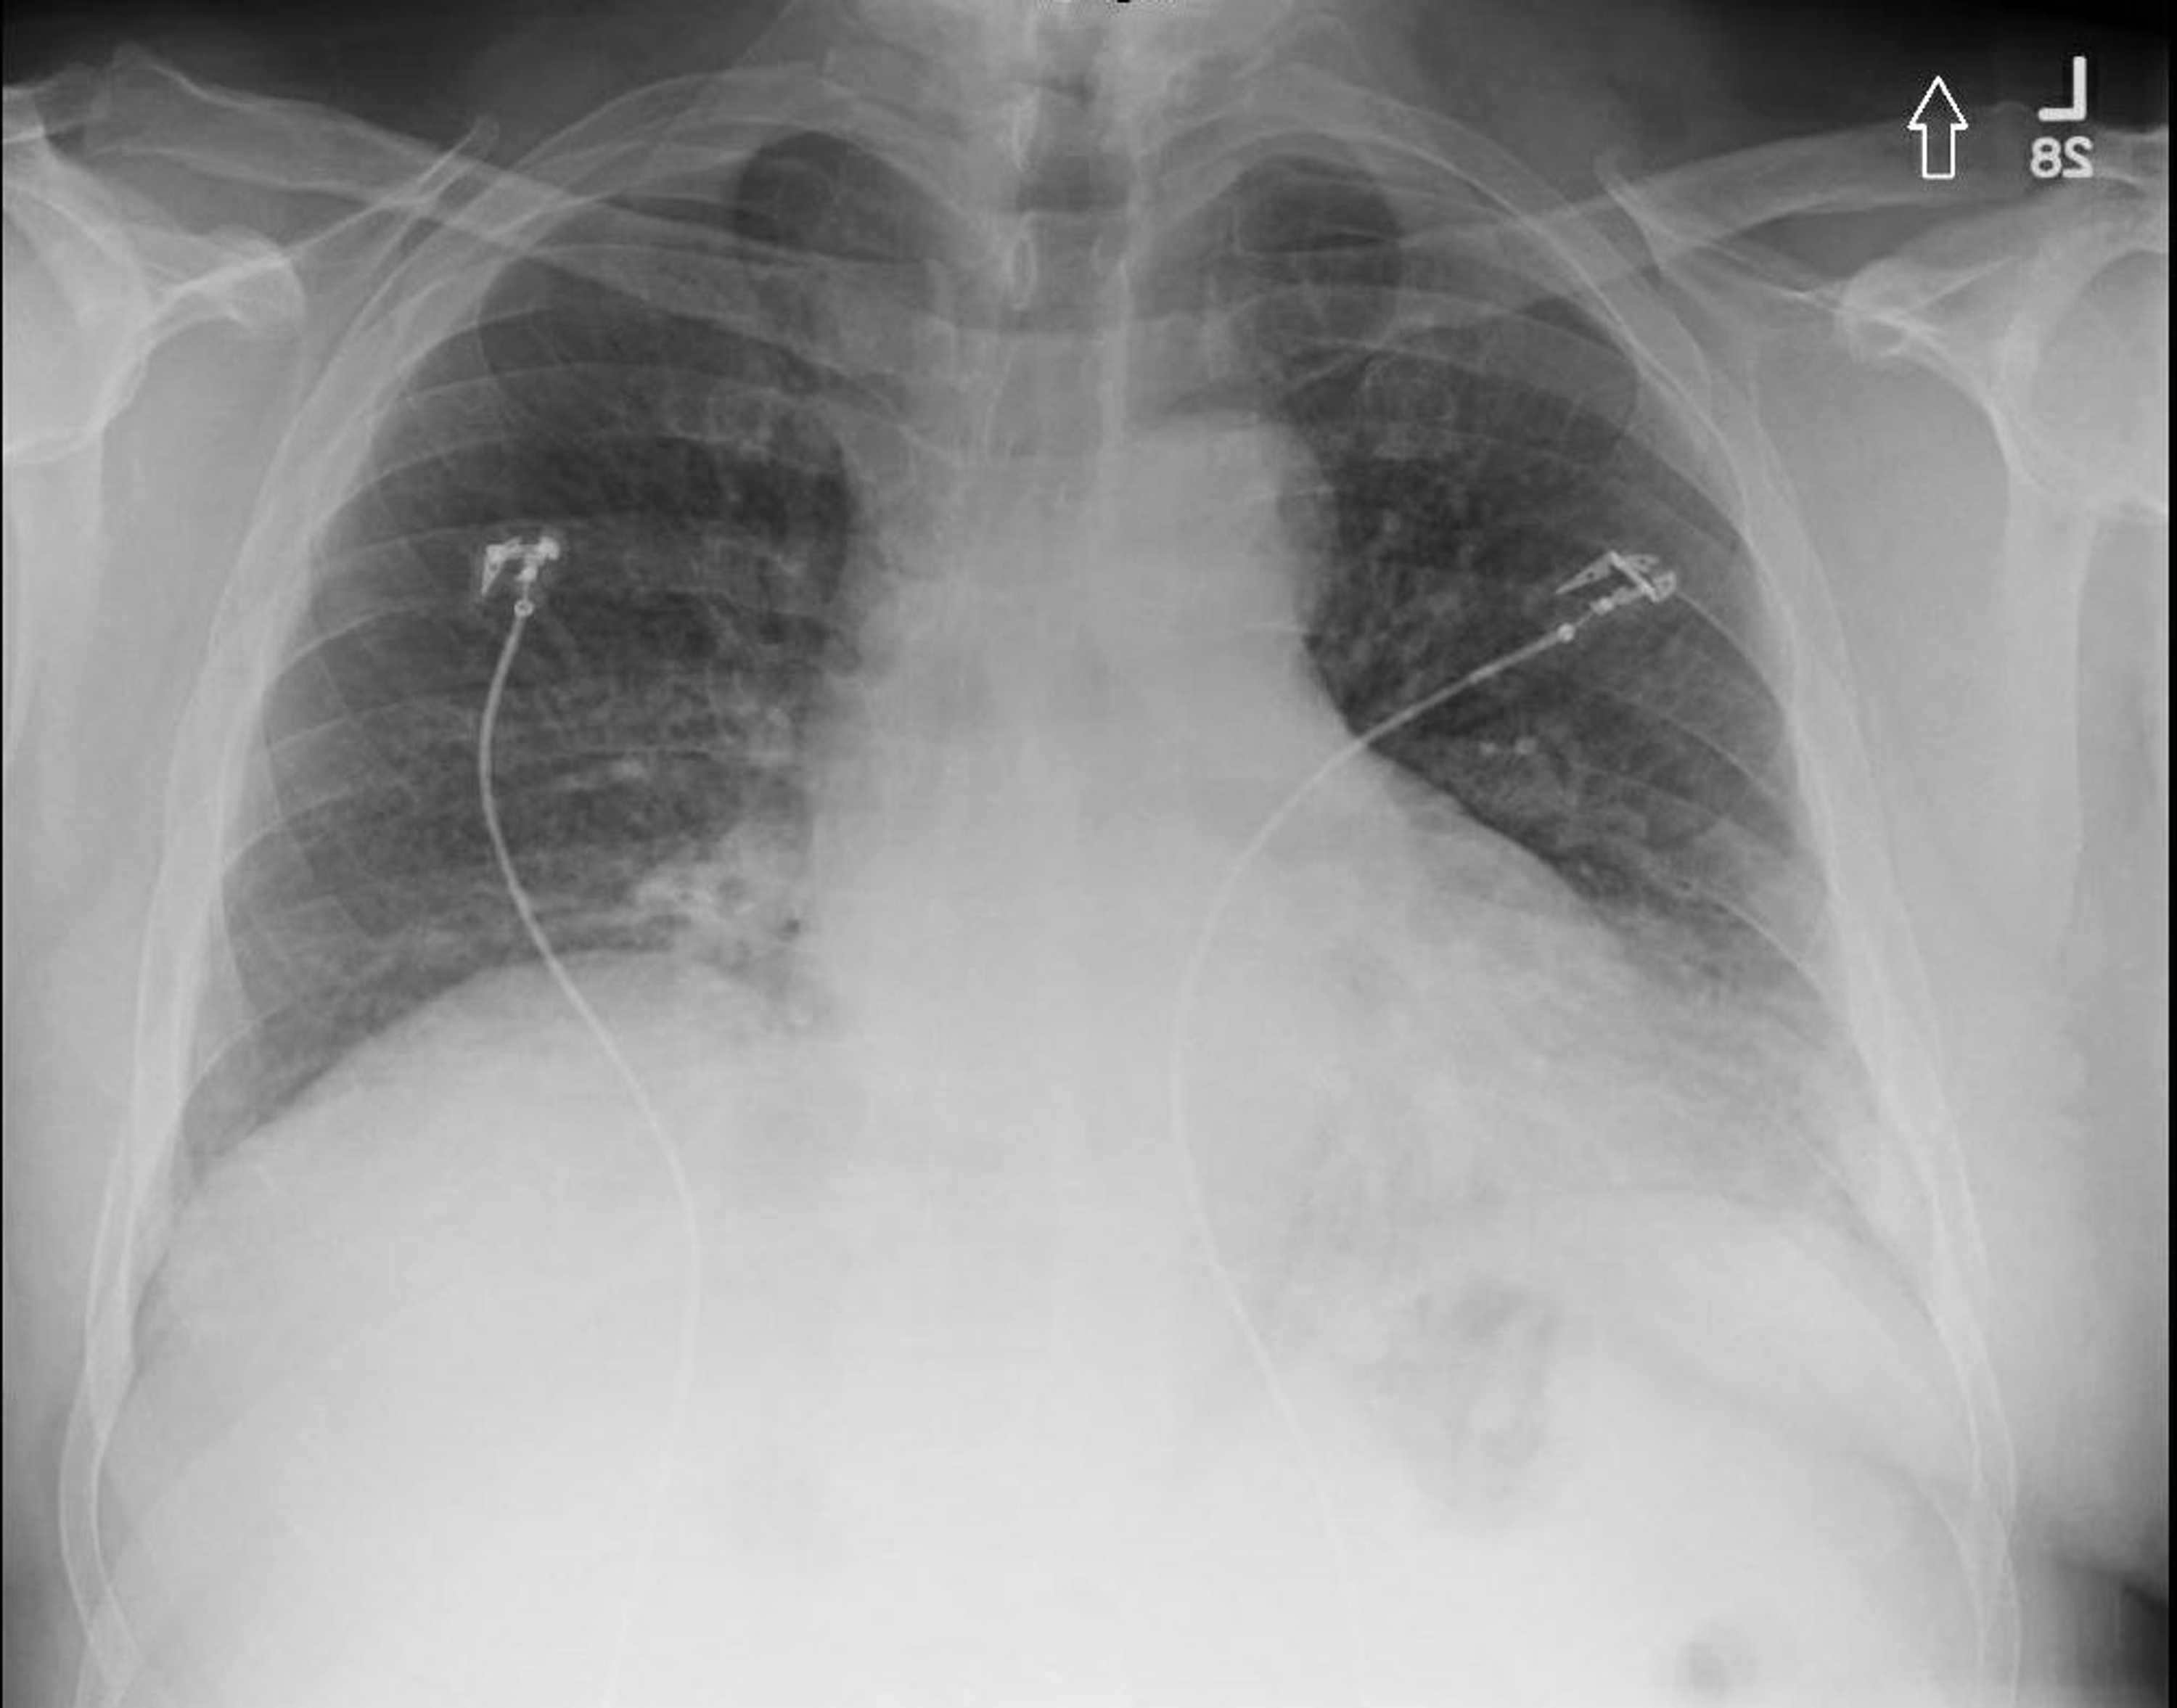

from www.cureus.com

Cureus Hidden Dangers of Severe Obstructive Sleep Apnea

Cureus Hidden Dangers of Severe Obstructive Sleep Apnea Sleep Apnea X Ray this guideline establishes clinical practice recommendations for the diagnosis of obstructive sleep apnea (osa) in adults and is intended for use in. Obstructive sleep apnea (osa) is characterized by. Symptoms are insidious and diagnosis is usually delayed. obstructive sleep apnoea (osa) is characterised by recurrent upper airway collapse during sleep resulting in chronic and repetitive hypoxia, hypercapnia, subsequent. Sleep Apnea X Ray.